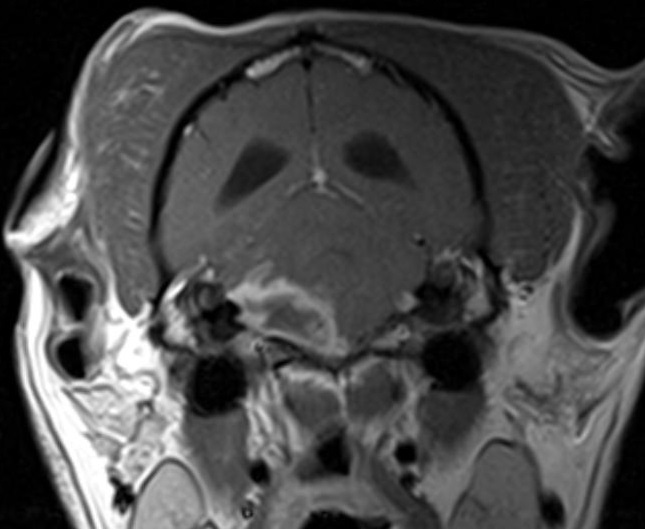

MRI 1

What are your differentials for this lesion?

This is a ring-enhancing lesion in the rostral brainstem. Differentials for ring-enhancement can be remembered with “MAGIC DR”

M: metastatic lesions

A: abscess

G: glial cell tumor

I: infarct (subacute)

C: cystic lesion (including cytic meningioma and other tumors) or resolving contusion

D: demyelination

R: radiation necrosis

HIV in humans include: lymphoma or toxoplasma

**This image was from a 10-year-old MC Sheltie with suspected cystic meningioma.